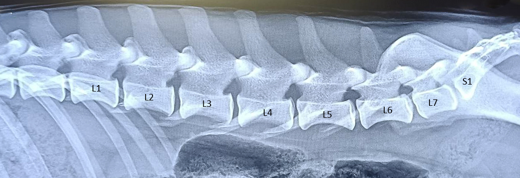

I väntan på att vi har en modell för Svenska Bretonklubben, uppmuntrar vi alla Medlemmar att i samband med HD-röntgen frivilligt även utföra en ryggröntgen för att öka kunskapen om frekvensen av LTV hos Bretoner. Det är en sidobild av ryggen till skillnad från HD-röntgen som tas från magen. Röntgenplåten skickas till Finska Kennelklubben (Kennelliitto) för analys och klassning av ev LTV. Självklart är det extra viktigt att hundar som planeras att användas i avel LTV-röntgas.

Normal Rygg, Namn